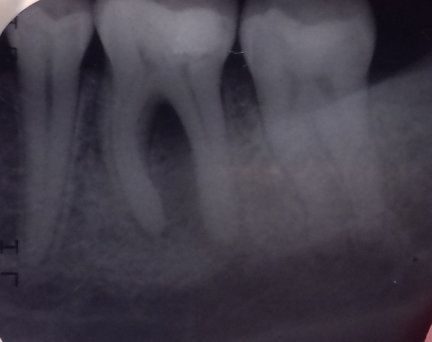

Здравствуйте. При принятии твердой и сладкой пищи, а также при ежедневной чистке зубов возникает ноющая боль в зубе (крайний левый на нижней челюсти). Стоматолог сказал, что есть небольшой кариес, поставили пломбу. Прошло уже три дня, а зуб всё равно ноет при накусывании. От чего это может быть и что делать в данной ситуации?

Добрый день . Скорее всего ваш стоматолог поставил неправильный диагноз или пломба завышает . Рекомендую обратиться на очный прием и после снимка вам все подробно расскажут. Не тяните , потеря времени может привести к потере зуба.